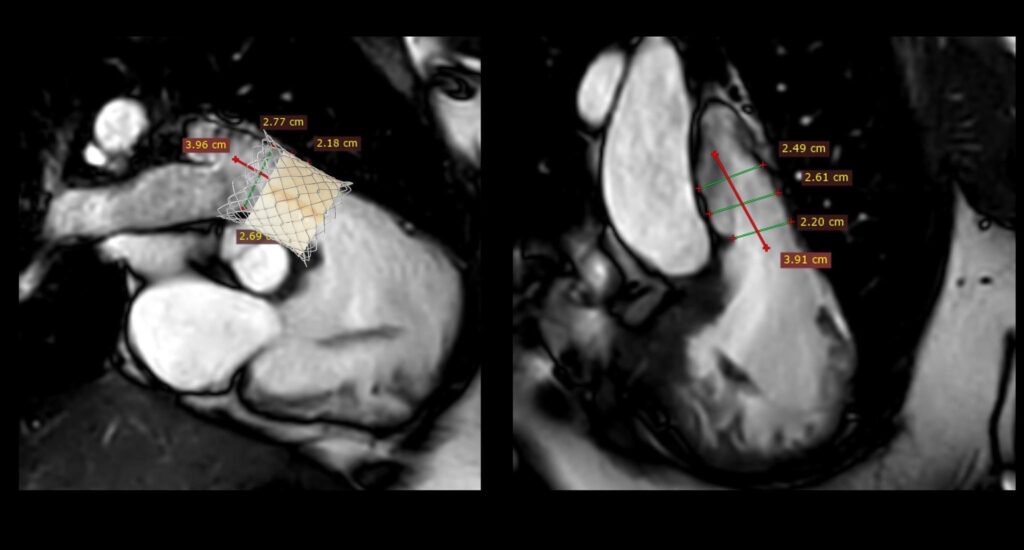

คณะแพทยศาสตร์ มช. สร้างความสำเร็จทางการแพทย์ ด้วยการรักษาโรคลิ้นหัวใจพัลโมนิกรั่ว (Pulmonary valve regurgitation) ผ่านสายสวน ในผู้ป่วยหญิงไทย อายุ 22 ปี ที่มีประวัติผ่าตัดรักษาภาวะ Tetralogy of Fallot มาก่อน และมีอาการของลิ้นพัลโมนิกรั่วรุนแรง

การใส่ลิ้นหัวใจพัลโมนิกเทียมผ่านสายสวนหัวใจ (Transcatheter pulmonary valve implantation; TPRI ) ในครั้งนี้ ทำผ่านทางหลอดเลือดดำใหญ่ บริเวณขาหนีบ จึงไม่ต้องผ่าตัดเปิดทรวงอก โดยกระบวนการรักษาและพักฟื้นผ่านไปได้ด้วยดี ไม่พบภาวะแทรกซ้อน ผู้ป่วยสามารถออกจากโรงพยาบาล 2 วันภายหลังการรักษา นับเป็นหนึ่งในความก้าวหน้าของนวัตกรรมการแพทย์เพื่อใช้รักษา ลดความเสี่ยงของภาวะแทรกซ้อนต่างๆ รวมถึงยกระดับคุณภาพชีวิตของผู้ป่วยได้

ผศ.นพ.กฤช มกรแก้วเกยูร อาจารย์ประจำแผนกโรคหัวใจ ภาควิชากุมารเวชศาสตร์ คณะแพทยศาสตร์ มหาวิทยาลัยเชียงใหม่ เปิดเผยว่า โรคหัวใจพิการแต่กำเนิดชนิด Tetralogy of Fallot มีความผิดปกติคือผนังหัวใจห้องล่างรั่วและหลอดเลือดในปอดตีบ ในประเทศไทยพบผู้ป่วยใหม่ประมาณ 300-500 รายต่อปี การรักษาผู้ป่วยในกลุ่มนี้คือ การผ่าตัดปิดรูรั่วผนังหัวใจห้องล่างและแก้ไขหลอดเลือดไปปอดให้หายตีบในช่วงอายุ 2 ปี

อย่างไรก็ตาม แม้ว่าจะทำการผ่าตัดไปแล้วในช่วงต้นของชีวิต แต่ผู้ป่วยจะยังคงมีภาวะลิ้นหัวใจพัลโมนิกรั่วตามมาได้อีกถึงประมาณร้อยละ 90 ส่งผลให้หัวใจห้องขวาต้องรับภาระหนักขึ้นและมีขนาดโตขึ้น จึงจำเป็นต้องรับการผ่าตัดอีกครั้งเพื่อแก้ไขลิ้นหัวใจพัลโมนิกรั่ว

การแก้ไขลิ้นหัวใจพัลโมนิกรั่วมี 2 วิธี คือ การผ่าตัดเปิดทรวงอกเพื่อใส่ลิ้นหัวใจพัลโมนิกเทียม และ การใส่ลิ้นพัลโมนิกผ่านทางสายสวนหัวใจ การเปลี่ยนลิ้นทั้งสองวิธีนี้เมื่อเวลาผ่านไป 10-20 ปี ลิ้นพัลโมนิกเทียมจะมีโอกาสเสื่อมอีก ทำให้ผู้ป่วยประมาณ 1 ใน 3 จำเป็นต้องเปลี่ยนลิ้นหัวใจซ้ำอีกครั้ง ซึ่งในผู้ป่วยบางรายอาจจะต้องการการใส่ลิ้นพัลโมนิกเทียมไม่ว่าจะโดยการผ่าตัดหรือผ่านทางสายสวน 2-3 ครั้งในช่วงชีวิตหนึ่ง

การผ่าตัดเปิดทรวงอกในแต่ละครั้ง จะก่อให้เกิดพังผืด (fibrous adhesion) เพิ่มความยากลำบาก และความเสี่ยงในการผ่าตัดมากขึ้น การรักษาผ่านทางสายสวนจึงเป็นทางเลือกที่จะลดความเสี่ยงนี้ลง อีกทั้งยังสามารถใส่ลิ้นพัลโมนิกเทียมชิ้นใหม่ทับแทนชิ้นเก่าได้ (valve in valve procedure)